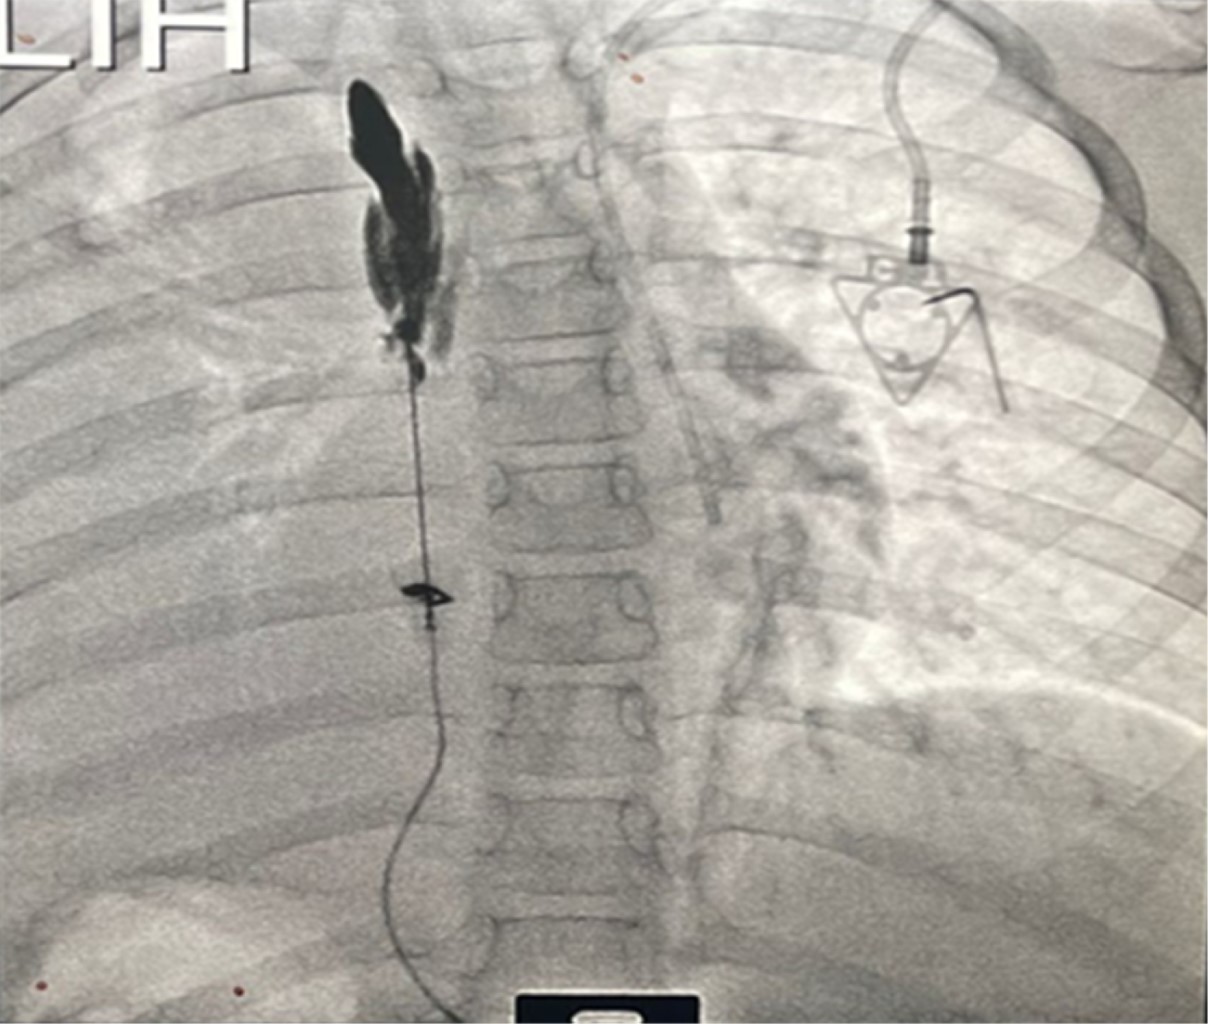

Masculino de siete años de edad, 30 kg de peso y 132 cm de talla, con diagnóstico de sarcoma de Ewing pleural izquierdo con compromiso de arcos costales 5, 6 y 7 izquierdos, con compromiso pleural y pericárdico, sin otros antecedentes de interés. Había recibido quimioterapia sistémica. El paciente ingresa el 01/10/2022 a urgencias por dolor de tipo pleurítico, sin asociarse a síntomas respiratorios. La tomografía axial computarizada (TAC) de tórax evidencia neoplasia infiltrativa de la pared del hemitórax izquierdo con extensión al hemidiafragma ipsilateral, pericardio, pleura parietal y visceral (Figura 1). En la resonancia magnética de tórax se encontraron nódulos aislados pleurales posteriores apicales izquierdos en relación con compromiso metastásico pulmonar. Desde el punto de vista oncológico, se determinó progresión de la enfermedad; por dolor severo del paciente, se consideró realizar neurólisis del plano del músculo erector de la espina, para lo cual se mantuvo al paciente con morfina 2 mg IV cada cuatro horas y rescates de 1 mg IV hasta cuatro en 24 horas en caso de dolor severo previo al procedimiento. A 10 días del ingreso a urgencias, el paciente fue llevado a manejo intervencionista del dolor; en decúbito prono, bajo previa asepsia y antisepsia, se realiza lavado quirúrgico, colocación de campos estériles, mediante guía ecográfica y fluoroscopía se identifican planos de apófisis espinosas torácicas (Figura 2), se situó central apófisis espinosa de T4, lateral a ella se identificó lámina y luego apófisis transversa con imagen en plano. Bajo anestesia general, se llevó la aguja a cuerpo de apófisis transversa y se colocó volumen de 20 cm3 en el plano del erector de la espina, identificando elevación del erector de la espina (Figura 3). No se presentaron complicaciones. Se realizó neurólisis unilateral del plano erector de la espina T4 izquierda con mezcla analgésica: 6 cm3 de alcohol al 99% + 4 cm3 de solución salina al 0.9% + 5 cm3 de bupivacaína al 0.5% sin epinefrina. Con adecuado control de dolor, posterior a procedimiento con FLACC (Face, Legs, Activity, Cry, Consolability) de 0, no requirió uso de rescate de opioides potentes, no presentó dolor incidental ni irruptivo y tuvo adecuado patrón de sueño. Posterior a esto, recibe radioterapia externa conformacional con intención paliativa. Dos días después del procedimiento, paciente con FLACC de 2 y al siguiente 0 con disminución del consumo analgésico. Por adecuada evolución clínica, se da egreso el 14/10/2022. Al mes control con adecuada evolución y FLACC de 0.

Figura 2